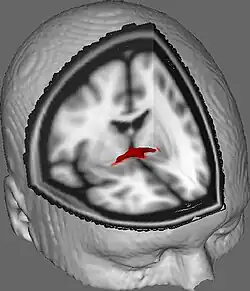

Coronal cross-section of brain showing the anterior commissure. (left, third from bottom.)